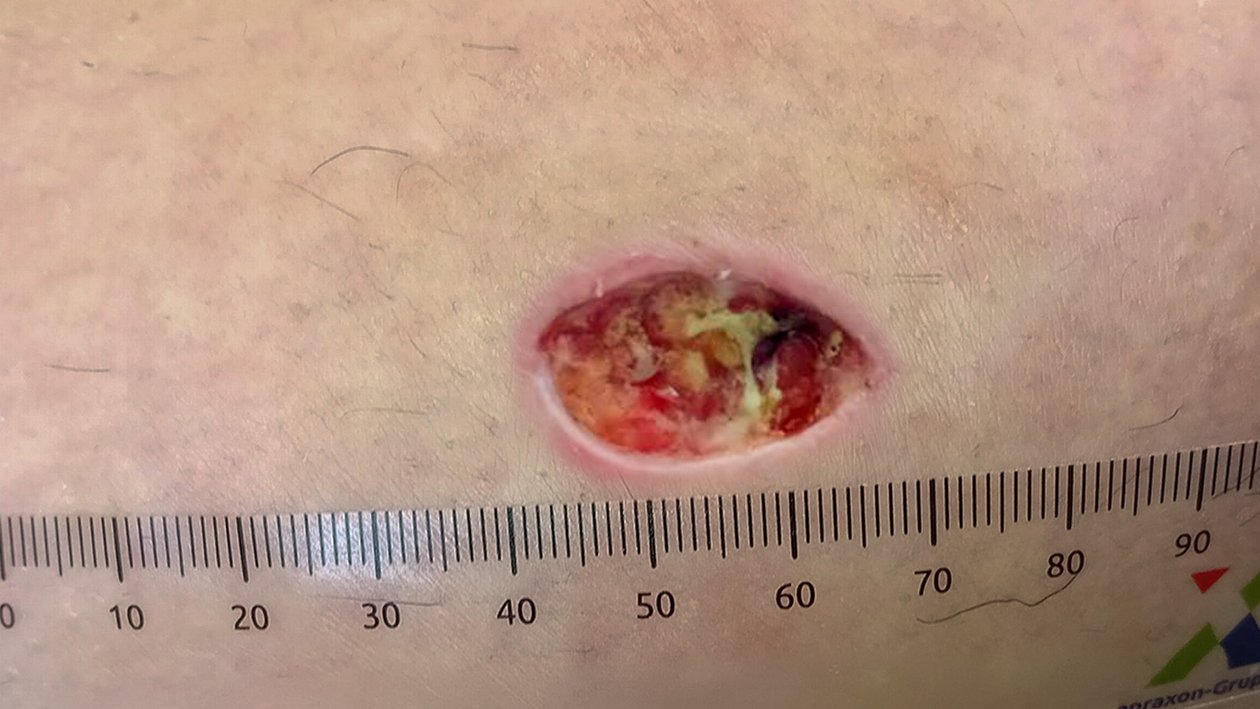

Foto 1

Die Wunde zeigt sich bei der Erstvorstellung als sekundärheilende Läsion am linken Unterschenkel (Wade) lateral. Sie ist 20 mm lang, 10 mm breit und bis maximal 14 mm tief (Foto 1). Der Wundgrund besteht aus subkutanem Fettgewebe mit Granulation und Fibrinbelägen. Der Wundrand ist leicht gerötet und geschwollen, die Wundumgebung unauffällig. Es besteht ein moderates Inaktivitätsödem. Die Exsudation ist gering, serös und trüb. Frau Dr. K. verspürt leichte Schmerzen bei der Wundreinigung (NRS 3). Ein Abstrich wird nicht entnommen.